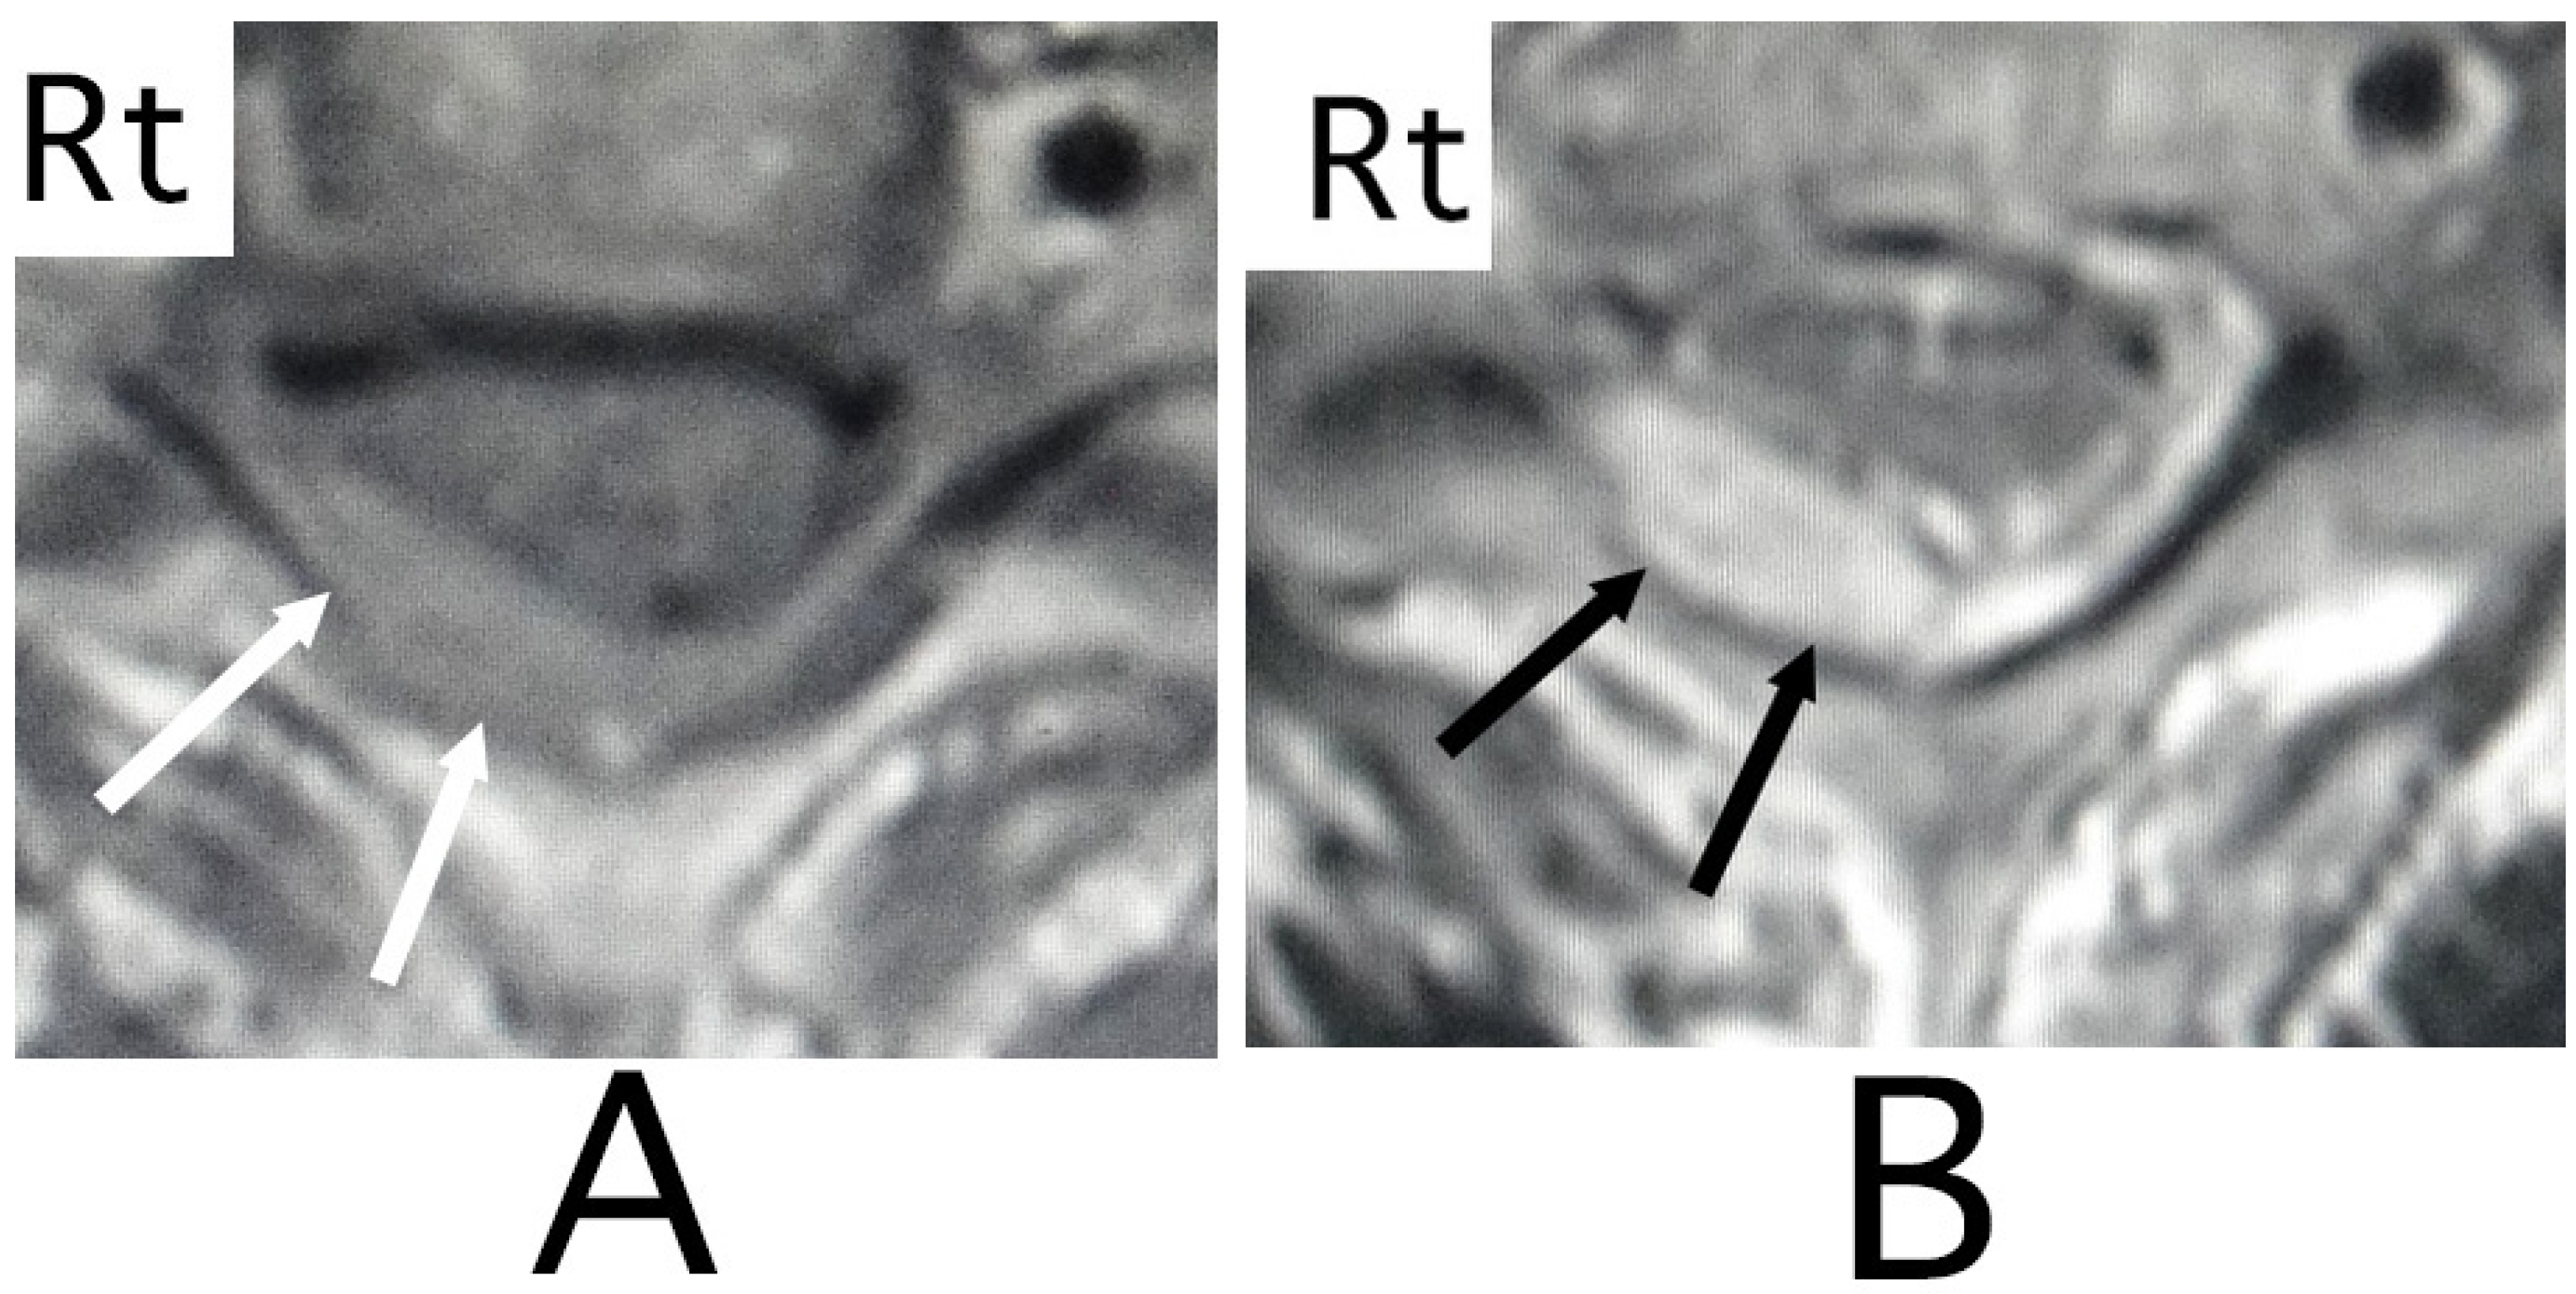

MRI of the spinal cord analysis was performed because the presence of acute lesions on the spinal cord was suspected, based on neurological findings and the clinical course. As a result, sagittal T1-weighted MRI showed an iso-intensity mass in the epidural space behind the spinal cord at the level from Th3 to Th6 (Figure 1A). Compression of the spinal cord was shown at the level between Th4 and Th6 (Figure 1A,B). The lesion was delineated as a high-intensity mass with heterogeneity and a superiorly adhered iso-intensity region in sagittal T1-weighted images (Figure 1B). Axial T1-weighted MRI showed an iso-intensity mass in the posterior part of the epidural space and a deviation of the spinal cord to the anterior direction (Figure 2A). The lesion was delineated as a heterogeneous high-intensity mass in axial T2-weighted MRI images (Figure 2B).

Figure 2. Axial MRI. An iso-intensity mass was identified in the posterior part in the epidural space (white arrows) (T1-weighted image; (A)). The lesion was delineated as a heterogeneous high-intensity mass (white arrows) (T2-weighted image; (B)). The spinal cord was compressed in the anterior direction (black arrows) (A,B). (Rt = right).